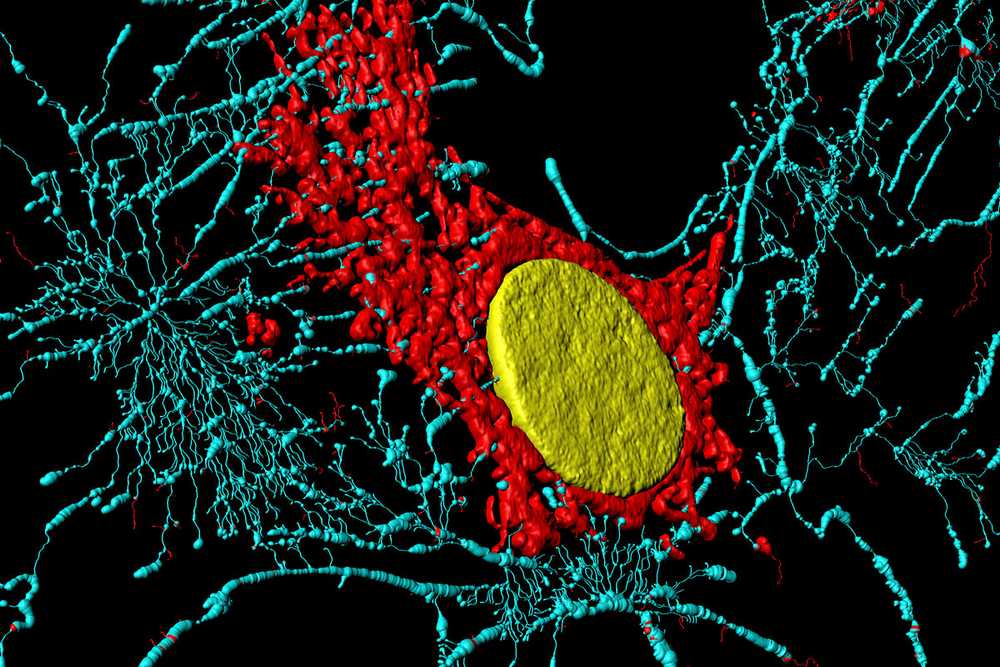

Ce vaste écosystème cellulaire – qui est finalement notre organisme – contient environ 250 types de cellules différentes. La grande majorité est soumise au renouvellement cellulaire, sauf quelques exceptions, comme, par exemple, les neurones et les cellules cardiaques où le renouvellement est très lent ou quasi inexistant.

Faisons un petit tour dans ce monde fascinant qui nous donne une meilleure compréhension des cellules, de notre corps, mais également des pathologies qui peuvent en résulter.